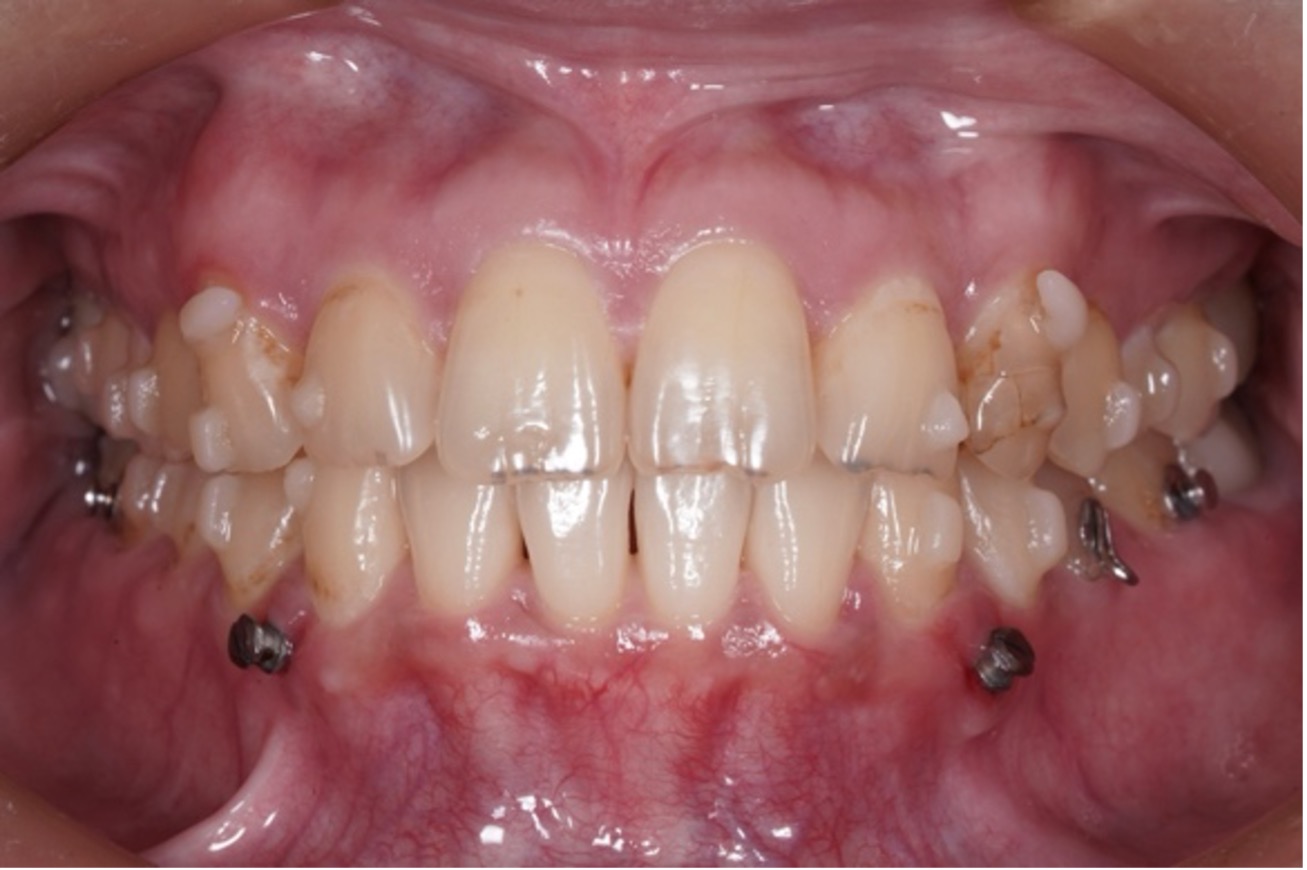

矯正治療の症例はこちら